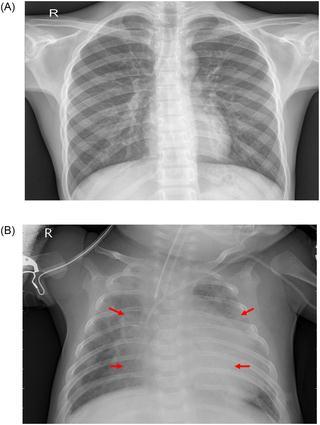

Medicalimagingtechniques,includingcomputedtomography(CT),magneticresonanceimaging(MRI),andchestradiography, are routinely employed to assist in the diagnosis of pneumonia. Among these modalities, chest X-ray imaging is widely preferredduetoitsnon-invasivenature,affordability,andaccessibility.Figure1illustratesrepresentativechestX-rayimages ofhealthyandpneumoniclungs.Infectedlungstypicallyexhibitabnormalopacities,knownasinfiltrates,whichappearas whiteregionsandserveaskeyindicatorsofpneumonia.Despitetheirclinicalusefulness,chestX-rayinterpretationsareoften influencedbytheexperienceandsubjectivejudgmentofradiologists,whichcanleadtodiagnosticinconsistencies[2].This limitationhighlightstheneedforreliableautomatedapproachestosupportpneumoniadetection.

Figure 1: ExamplesoftwoX-rayplatesthatdisplay(a)ahealthylungand(b)apneumoniclung.Theredarrowsin(b)indicate whiteinfiltrates,adistinguishingfeatureofpneumonia.TheimagesweretakenfromtheKermanydataset